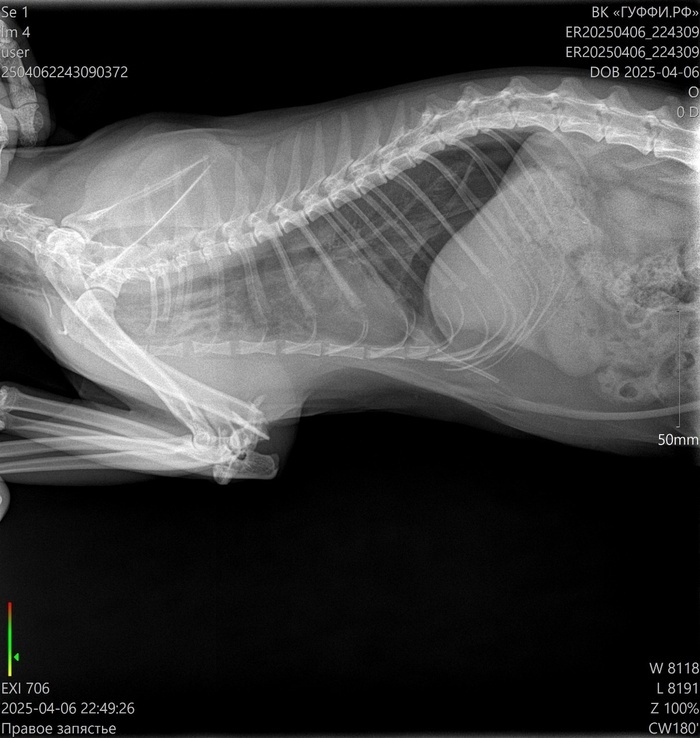

Верю, что тут есть профильные специалисты. Позавчера не уследил за кошкой, забыл закрыть форточку на какие-то полчаса, выпрыгнула с пятого этажа и крайне неудачно. Переломаны левые передняя и задняя лапы. Но если по задней лапе прогноз хороший, то по передней хирург сказал, что сустав раздроблен, и конечность он будет сращивать жестко и под углом. Кошке всего полтора года, очень жизнерадостная - даже под опиоидным обезболивающим уже сегодня сама сходила по-маленькому, и пытается встать и бегать за остальными двумя кошками (у нас их три).

Можно ли по рентгеновским снимкам определить - удастся ли сохранить подвижность лапке? Если искать хирурга, который за это возьмется.